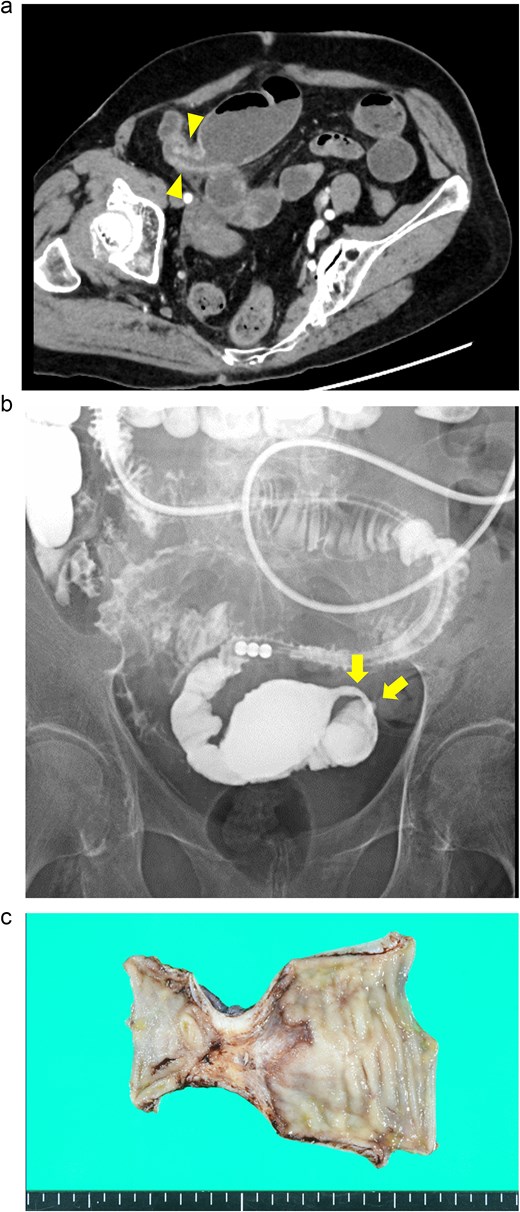

An 88-year-old woman presented with recurrent episodes of epigastric pain. Three months prior, she experienced similar abdominal pain, and CT revealed HPVG and mesenteric emphysema without mesenteric ischemia or bowel strictures. The patient’s symptoms resolved with conservative treatment, and none of the CT features remained by the follow-up. Her vital signs were stable, and most of the laboratory test results were normal, including WBC count (6700/μl), CRP concentration (0.95 mg/dl), Hb level (12.3 g/dl), and Lac concentration (0.9 mmol/L). However, her blood glucose level (BGL) was elevated (315 mg/dl), as was her glycated hemoglobin (HbA1c) level (9.0%). Contrast-enhanced CT revealed a segmental luminal stricture with wall thickening in the distal ileum, suggestive of bowel obstruction (Fig. 2a). A long intestinal tube was placed for luminal decompression, and fluoroscopy confirmed the presence of segmental, smooth luminal narrowing in the distal ileum (Fig. 2b).

Case 2: (a) Contrast-enhanced CT of the abdomen. The arrowheads indicate segmental luminal stricture with wall thickening in the distal ileum. (b) Fluoroscopy with a long intestinal tube. The arrows indicate a segmental, smooth luminal narrowing in the distal ileum. (c) Macroscopic view of the resected specimen. Circumferential ulceration and surrounding fibrosis are visible in line with the stenotic site.

Exploratory laparoscopy revealed an 8-cm-long bowel stricture with segmental induration 30 cm from the ileocecal valve, which was resected. The pathological specimen revealed circumferential ulcer formation at the stenotic site, accompanied by granulocyte infiltration and fibrosis extending from the submucosa through the proper muscle layer. No signs of tumors or IBD were noted (Fig. 2c). The postoperative course was uneventful, and she was discharged on the eighth postoperative day. By the 16-month follow-up, she had not had any recurrences of abdominal symptoms.